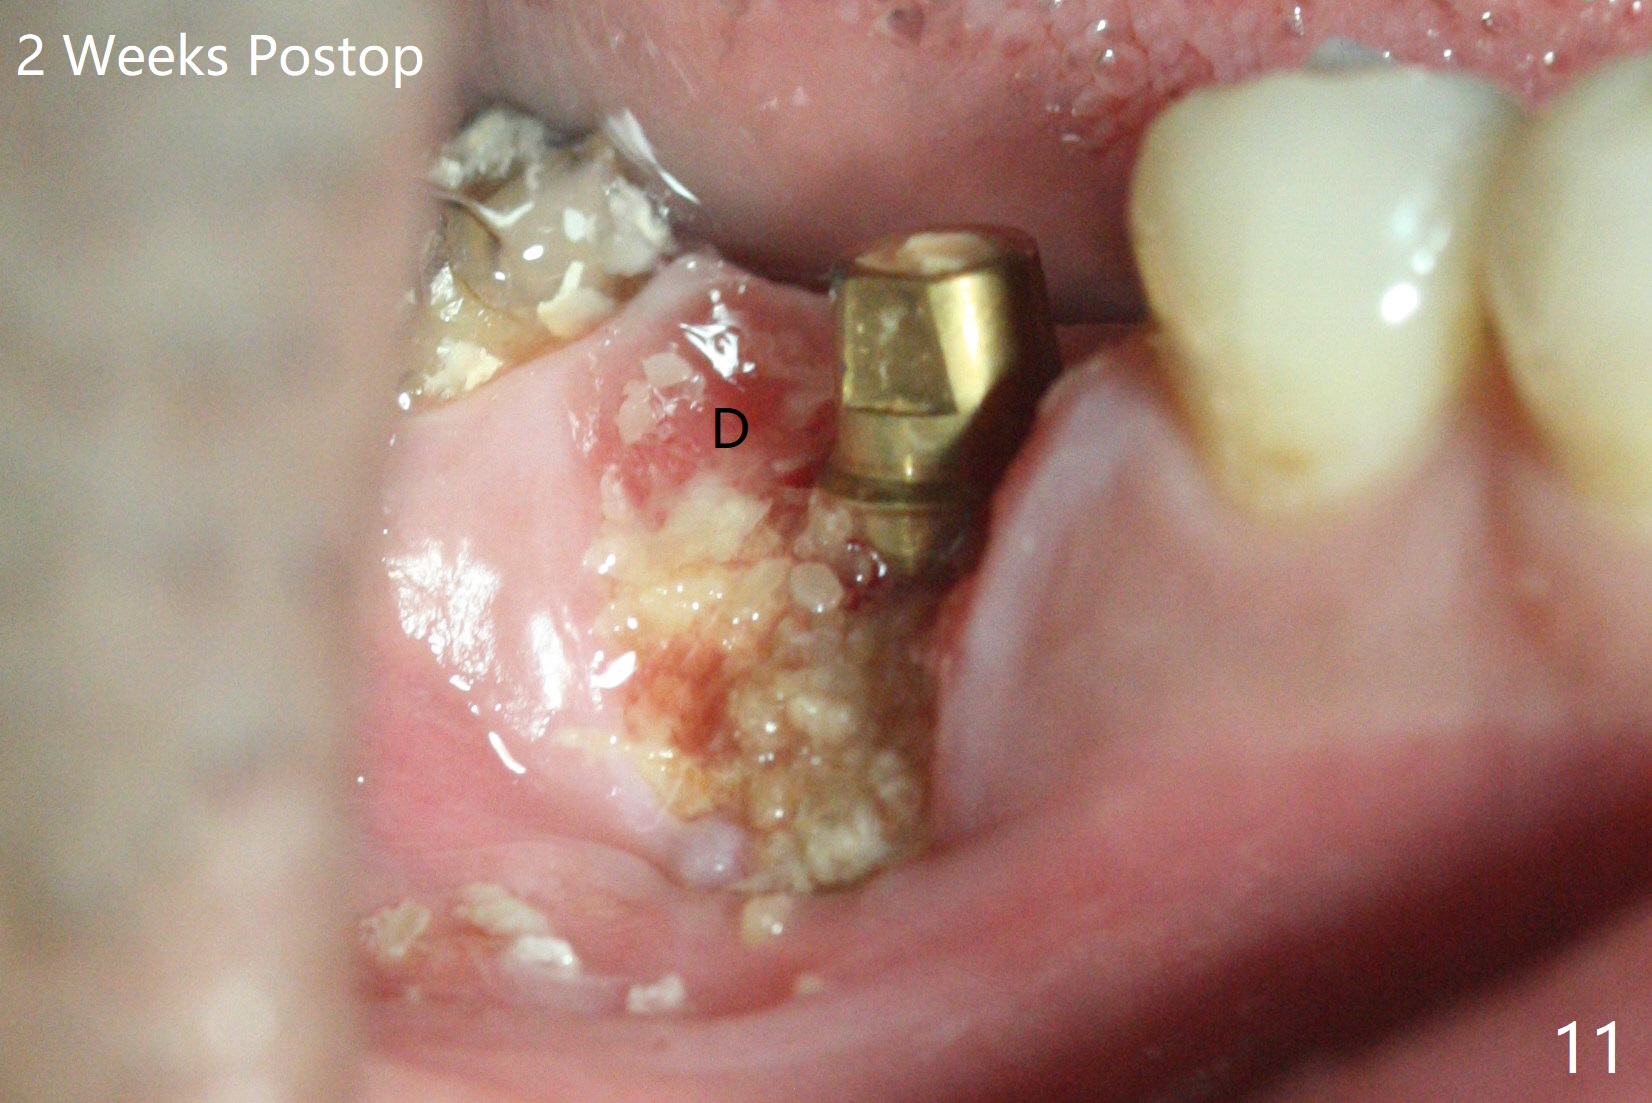

When the tooth #30 is extracted, the gingiva buccal to the septum (S in Fig.1,2 (P: papilla between the mesial and distal roots)) collapses. The latter is fixed with placement of a 4.5x11.5 mm implant (with guide), a 5.2x4(5) mm cemented abutment (Fig.3) and mixture of cortical bone (125μm – 850μm) and cortical/cancellous bone (.5-1 mm) with PRF (sticky bone, B in Fig.4-6). After placement of 2 pieces of PRF membrane over the bone graft, a temporary crown is fabricated to cover the buccal defect (Fig.7 T). Approximately 7.5 mm of the buccal threads are covered by the thick layer of bone graft (Fig.8 B). It is amazing to expect that the bone graft will turn into the buccal plate. It would be better if a narrower implant (4 instead of 4.5 mm) were placed more lingually or there were < 4 mm implant thread exposure (Fig.9). The gingiva reacts to the provisional nicely 7 days postop (Fig.10). The provisional will be removed for modification in 1 month. The patient complains of bad smell from the provisional 2 weeks postop. The provisional is removed. The distal socket (Fig.11 D) is healing, whereas the buccal bone graft (Fig.12 B) seems not have been vascularized. Pedicled flaps (I) should be transferred to cover the buccal bone graft. The margin of the provisional is polished, becomes short, and covered by periodontal dressing, which dislodges 2 days later. One week later, granulation tissue is forming apically with use of oral antibiotic and water jet (Fig.13 *). The bad smell reduces. The superficial loose bone graft changes colar and becomes detached 1 month 10 days postop. The temporary crown with the shortened buccal shelf is reseated for self cleansing or reapplication of PRF if needed (Fig.14).